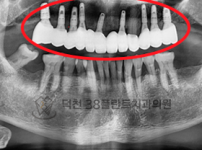

치료전후